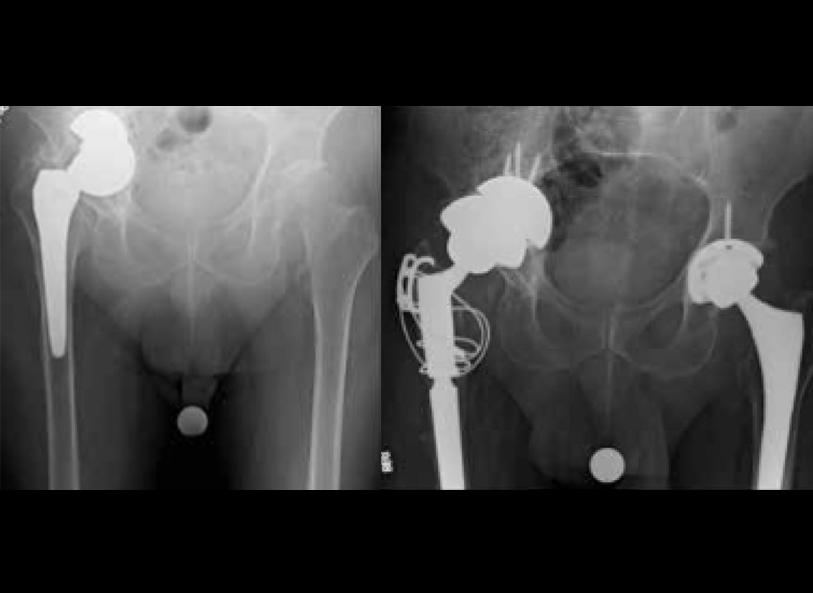

Joseph Park, MD, who serves on the board of directors for the American Orthopaedic Foot & Ankle Foundation, describes a case involving a woman in her late 60s with severe bilateral ankle arthritis and valgus (pronation) deformity. “This patient was an otherwise very healthy woman with a history of severe arthritis in both ankles. The condition was so extreme that the bones in her ankles had collapsed leading to severe tilt of the talus within the ankle joint. She’d tried other treatments, including bracing, injections, and physical therapy, but she was now unable to walk for even short distances without severe pain.”

After arriving at UVA Health, total ankle replacement was suggested as the best treatment option to restore function and minimize pain. According to Park, even severe deformities can be addressed through ankle replacement and realignment due to improved implant technology and innovations in surgical techniques.